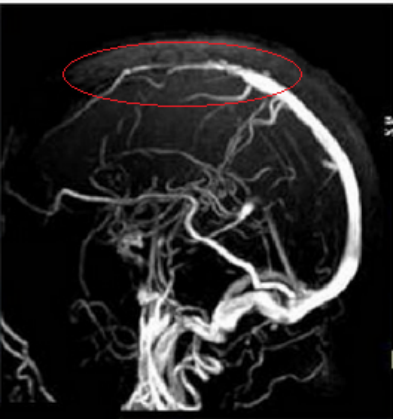

紅圈內的靜脈竇明顯變細,提示靜脈竇血栓

醫(yī)生給小強解釋道,人體腦部的血液供應來自雙側頸動脈與椎動脈,這四根腦動脈好比是家里的四根“水管”,負責將水(血)送到家里(大腦)供日常使用,用完的廢水再通過下水道排出去。靜脈竇就像是大腦的“下水道”,負責將靜脈血引流至心臟進行再利用。如今下水道堵塞了(腦靜脈竇血栓導致),用完的廢水排不出去,引起家里(大腦)積水,導致腦內壓力增高,形成顱高壓,進而出現頭痛、癲癇等病癥,嚴重者會導致腦出血甚至死亡。